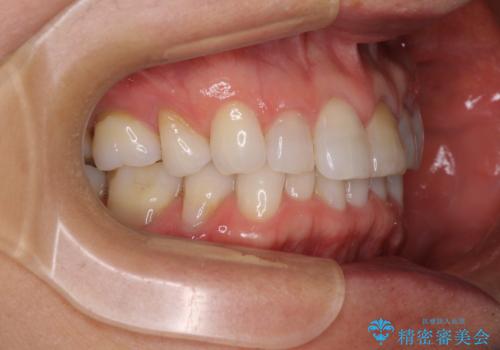

矯正治療の後戻り インビザライン・ライトでの再矯正

- 上下前歯を中心に、以前行った矯正治療の後戻りが気になるとのことで来院された患者様です。

後戻りは軽度であったため、インビザライン・ライトにて治療を行うこととしました。

矯正治療後は、再度後戻りすることを極力回避するために、下顎前歯の舌側を細いワイヤーを用いて保定することとしました。